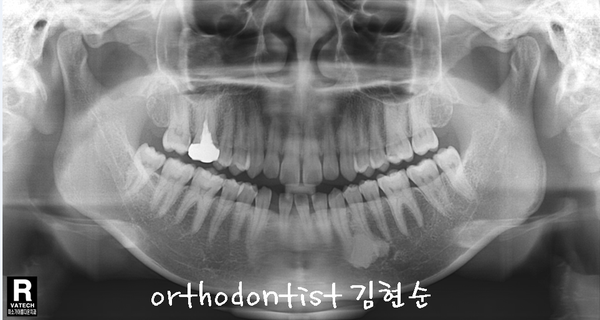

- Treatment plan -

-

치아 사이 공간 해결, 상실 공간 보철 위한 비발치 교정

#42 치아 공간을 벌리고 보철해야 좌우 대칭과 교합이 맞음

상하 교정 장치 부착 → #42 open → 교정 마무리 시기에 implant

예상 교정 기간 약 7 ~ 9 개월